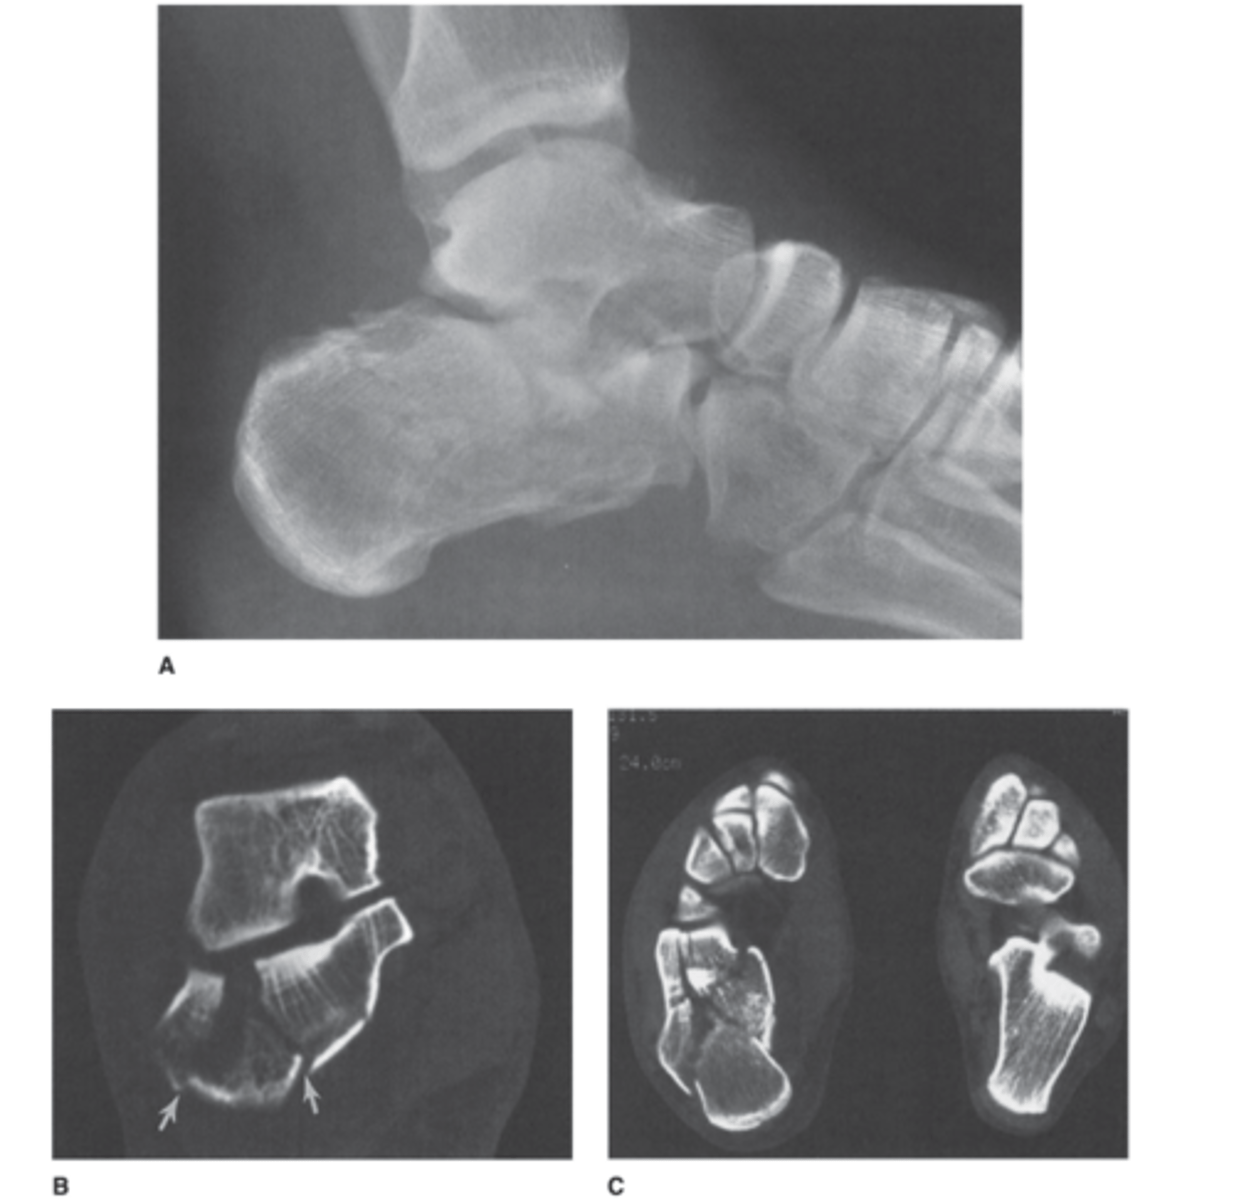

Where is the fracture here? This is the x-ray and CT

Answer

Calcaneal fracture. It is comminuted. We cant really see the degree to which it is involved on the x-ray.

CT is showing oriented fracture lines entering the posterior facet of the posterior and middle subtalar joints.

There is also a comminuted fracture of the calcenocuboid joint.

Moral of this: note how well the CT confirmed this for you